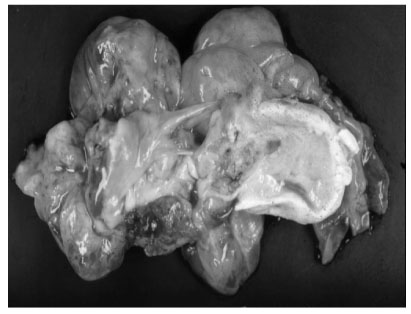

Fig 1). An explorative laparotomy revealed a 9 × 8 cm, globular encapsulated mass, located between the greater omentum and transverse mesocolon, and a 1 cm, ovoid nodule in segment IV of the liver. The mass showed no evidence of invasion of adjacent organs. Both ovaries were normal at the time of surgery. The mass was completely excised surgically, and the hepatic lesion underwent wedge resection. Grossly, the tumor was a 10 × 9 cm, whitish to gray, globular solid mass (

Fig. 2); sectioning revealed semisolid grayish material and cartilaginous tissue. Pathologic examination revealed a mixed malignant GCT made of two components, a mainly endodermal sinus tumor and a small mature teratoma. We also observed a loose reticular pattern and rounded papillary processes with central capillary, Schiller-Duval bodies. The tumor was immunohistochemically positive for AFP. The resected hepatic specimen was a metastasis of the mixed GCT and was histologically identical to that component of the primary tumor (

Fig. 2Gross appearance of the resected tumor. The tumor appears as a whitish to gray globular solid mass, measuring 10 × 9 cm. The cut surface shows semisolid grayish material and cartilaginous tissue.